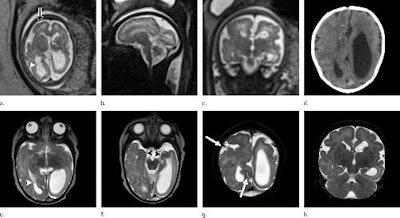

While microcephaly is a hallmark of Zika, and most fetuses underwent at least one imaging examination that showed head circumference below the fifth percentile, there are a number of other brain abnormalities that indicate the presence of the disease, according the article. These include abnormalities in ventricular size, gray- and white-matter volume loss, abnormalities in the brainstem, and calcifications.

In addition, 94% of the fetuses in the confirmed Zika group had abnormalities of the corpus callosum, a condition found in 79% of the presumed Zika group. All but one had abnormalities in cortical migration, which means that neurons didn't travel to the proper location in the brain.

What's more, almost all the neonates had intracranial calcifications, most often at the gray-white junction of the brain. And all neonates showed varying abnormalities in cortical development, according to the report.

"The severity of the cortical malformation and associated tissue changes and the localization of the calcifications at the gray-white matter junction were the most surprising findings in our research," said Dr. Fernanda Tovar-Moll, PhD, in a statement released by RSNA.

Other signs of Zika infection in neonates included a collapsed appearance of the skull, with overlapping sutures and redundant skin folds. These unusual characteristics could be caused by the small brain as it develops, but they also could be due to potential ventriculomegaly leading to a larger head size that then decompresses, and/or brain atrophy that gives the skull a collapsed shape.